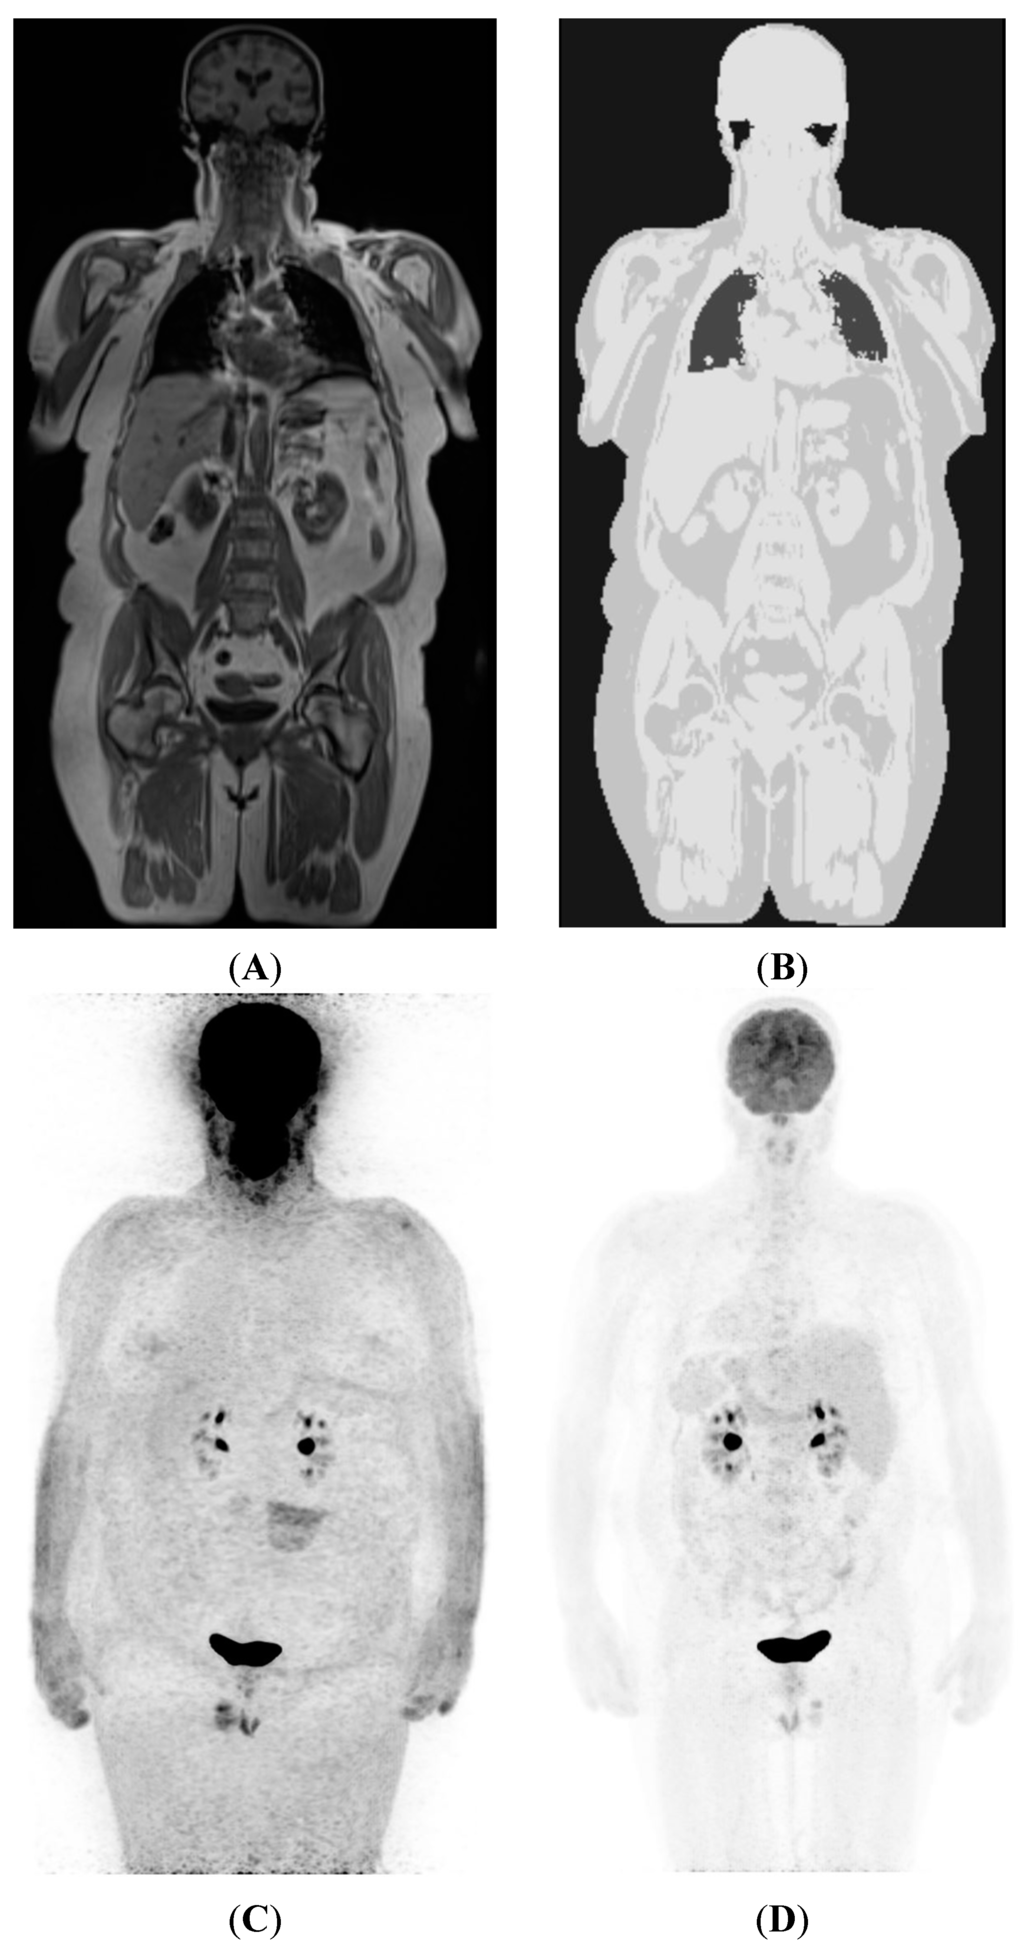

2.4. Attenuation Correction in PET/MRI

3. Imaging Protocols and Workflow